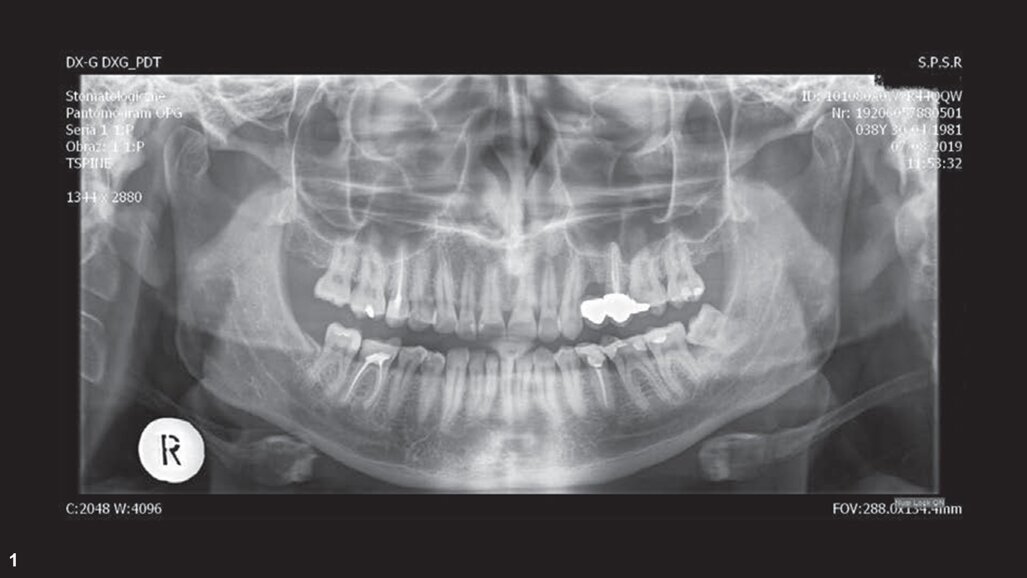

检查发现26对冷、甜刺激产生疼痛。全景片显示龋已穿髓(图1)。

笔者选择进行单次的牙髓治疗。首先进行局部麻醉给药和橡皮障隔离。之后使用金刚砂车针开髓,并用超声工作尖(CAVI 2-D,VDW)找到根管口。开髓过程中使用探针探查到4个根管。腭根管的工作长度为21.5mm(C-PILOT,ISO 10号,VDW),近颊根管和远颊根管的工作长度为21.0mm(C-PILOT,ISO 10号),近颊第二根管的工作长度为20.0 mm(C-PILOT,ISO 8号)。使用电子根尖定位仪对工作长度进行确认。从全景片和牙片(图2)上可以发现,根管十分狭窄、弯曲,因此笔者决定使用连续旋转根管预备系统(VDW.ROTATE,VDW)。

图2:初始X线片。